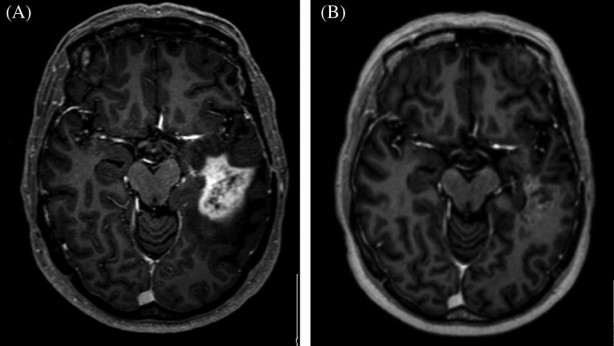

Lisansüstü öğrencisi Yasuhito Mitsuyama ve Doçent Daiju Ueda liderliğindeki araştırma ekibi, ChatGPT gibi büyük dil modellerinin diğer tanısal görüntüleme alanlarındaki potansiyelini daha derinlemesine araştırmaya hazırlanıyor.

Amaçları ise doktorların yükünü hafifletmek, teşhis doğruluğunu artırmak ve daha iyi eğitim ortamları için yapay zekayı kullanmak.